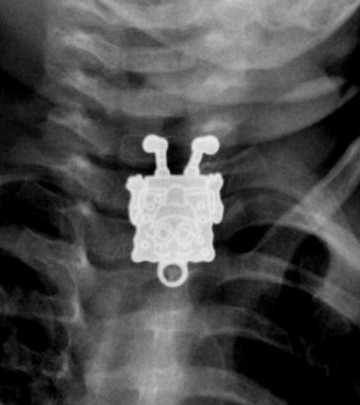

1. Кулон со Спанчбобом, случайно проглоченный неудачливым жителем

Саудовской Аравии.